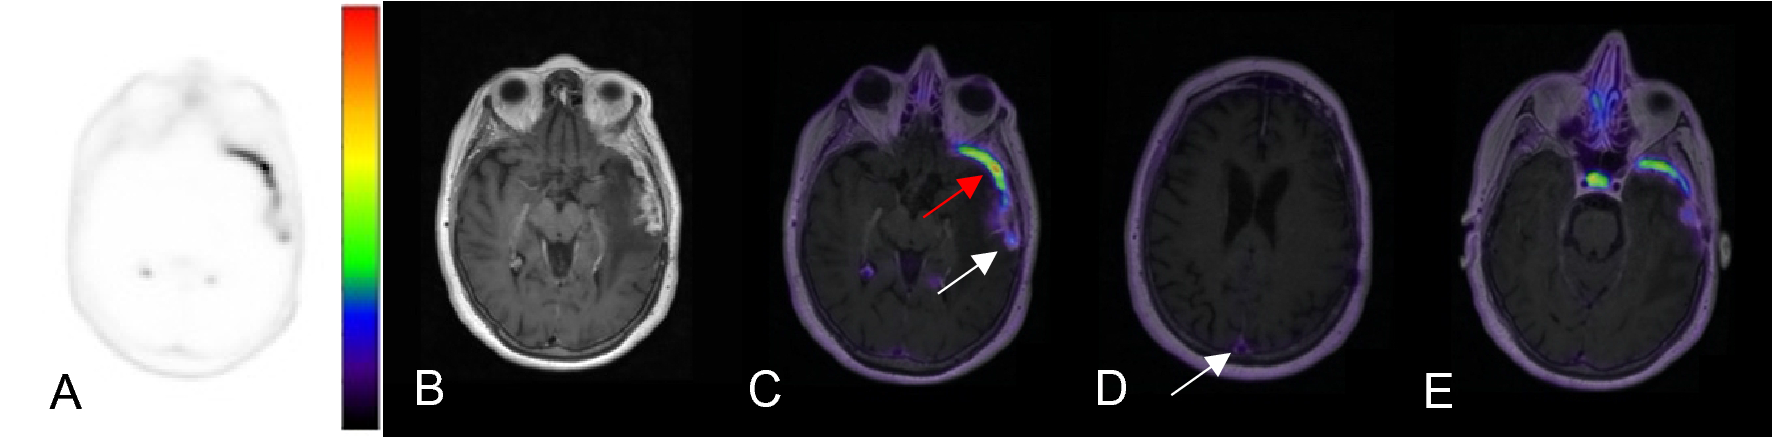

Figure 2

Axial images of [68Ga]-DOTATATE PET AC (A), 3D T1 post-gadolinium MR (B), fused PET/MR T1 (C–E) windowed SUV 0–15. This representative patient from the cohort is a 70-year-old female with a history of WHO grade II meningioma s/p resection and proton therapy 6 years prior to imaging and an additional proton therapy a year prior. The fused PET/MR images demonstrate a lesion suspicious for a meningioma in the left anterior temporal pole with SUV of 13.6 (C, red arrow). The more posteriorly located enhancing lesion (C, white arrow) demonstrates SUV of 4.5 and was suspicious for post-treatment change, given that the SUV of the superior sagittal sinus was 2.3. The subsequent resection and biopsy of the two lesions a year later confirmed the suspected diagnosis of recurrent meningioma and radiation necrosis, respectively. The superior sagittal sinus (D, arrow) demonstrates SUV of 2.3 and the pituitary gland (E) demonstrates SUV of 12.4.